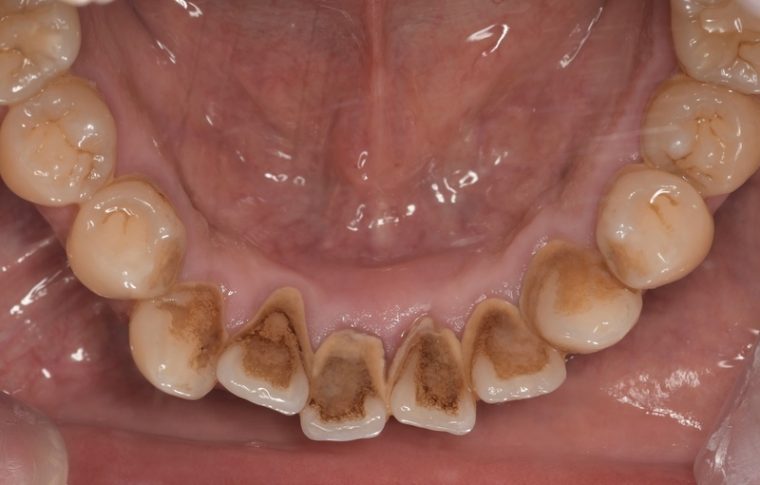

Before①

Before②

| 年齢・性別 | 38歳・男性 |

| 主訴 | 下顎 歯石除去したい |

| 治療内容 | スケーリング |

| 治療期間 | 30分 |

| 治療費 | 約1,500円(保険診療) |

| リスク・副作用 | 知覚過敏、歯肉退縮 |

| 治療方針 | 歯肉縁上歯石を除去してから歯肉縁下歯石を除去します。ご自身でのプラークコントロールができるようになったら定期検診に移行します。 |

| 担当者所見 | 半年ぶりの歯科医院の受診。歯石が付きやすいためセルフケアの重要性をお伝えして、定期的にクリーニングを行います。出血率が高く炎症が強いため、今後はセルフケアを強化して歯周病治療を行います。 |